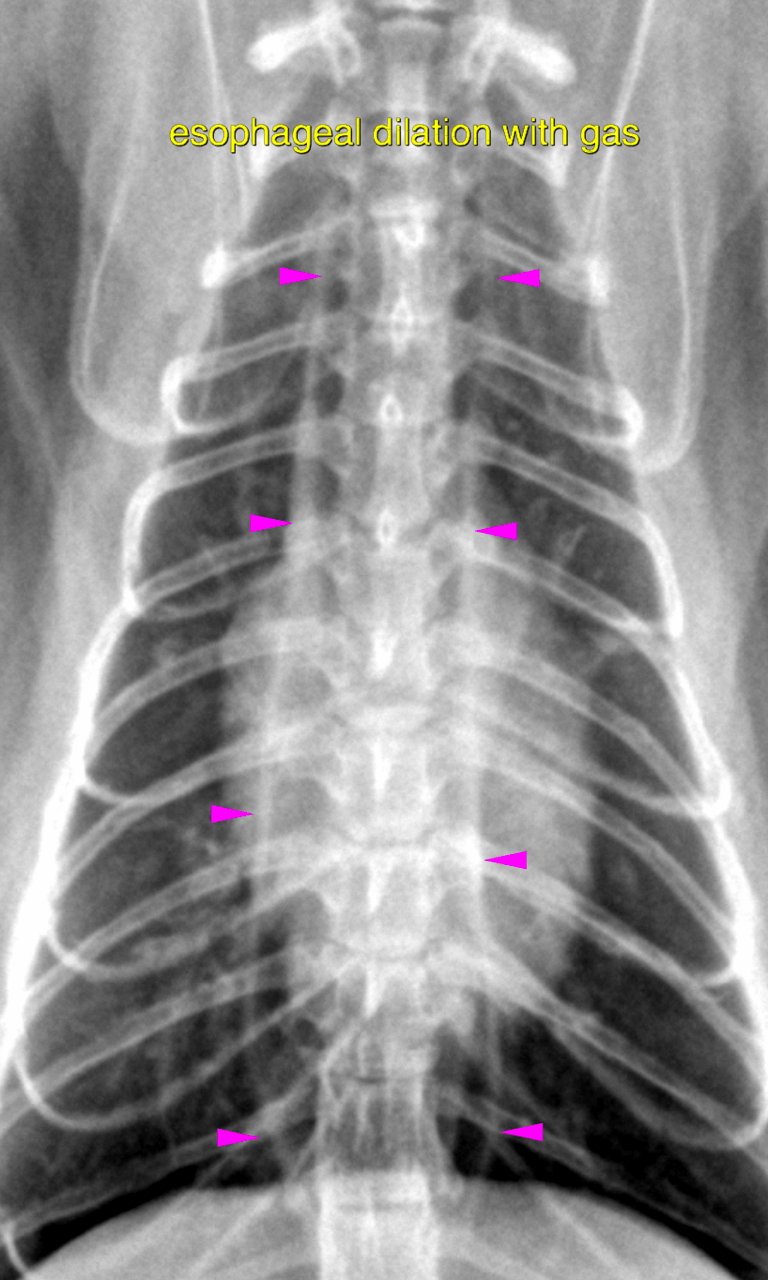

lateral and vd thorax – There is no evidence of an

abnormal pulmonary infiltrate throughout the lungs.

Moderate generalized dilation of the intrathoracic esophagus with gas is noted. The

stomach is moderately distended with gas. The gastric wall tone appears to be low.